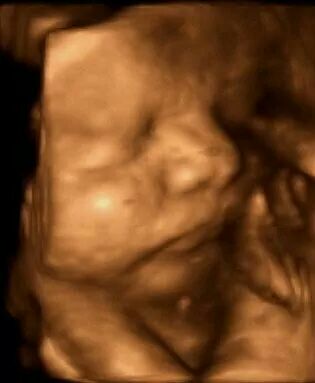

Having a baby

Dr Emma Buckland is an experienced obstetrician who enjoys managing both high and low risk pregnancies. Her main focus is the health of mother and baby at all times, but having said that, she is happy to allow nature to take it’s course during the birth process and encourages active labour and vaginal birth. She will support women in their decision to have a vaginal birth after cesarean, a vaginal breech birth, or vaginal birth of twins. She also offers External Cephalic Version (turning a breech baby in the womb). Sometimes a caesarian birth, an epidural or an assisted birth is needed and this is a decision made after discussion with the couple. As Emma delivers less than 10 babies per month in her private practice she has the time and energy to get to know each couple and to work with each mother to provide individualised care.

Emma prefers to meet her pregnant patients at about 8 weeks of pregnancy to confirm the pregnancy is going well and organise early tests.